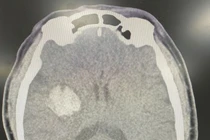

dot-quy-an-cung.jpg

Bác sĩ Khoa Cấp cứu thăm khám cho bệnh nhân uống An cung ngưu hoàng hoàn chữa đột quỵ - Ảnh BVCC

Cần nhấn mạnh rằng, yếu tố tiên quyết trong điều trị đột quỵ không phải là một viên thuốc thần kỳ, mà là thời gian đưa người bệnh đến cơ sở y tế chuyên khoa. Giờ vàng trong đột quỵ là từ 3 đến 6 giờ đầu kể từ khi xuất hiện triệu chứng. Trong thời gian này, việc chụp CT/MRI sọ não sẽ giúp xác định loại đột quỵ (nhồi máu hay xuất huyết), từ đó bác sĩ có hướng điều trị đúng: Tiêu sợi huyết, can thiệp nội mạch hoặc điều trị nội khoa.